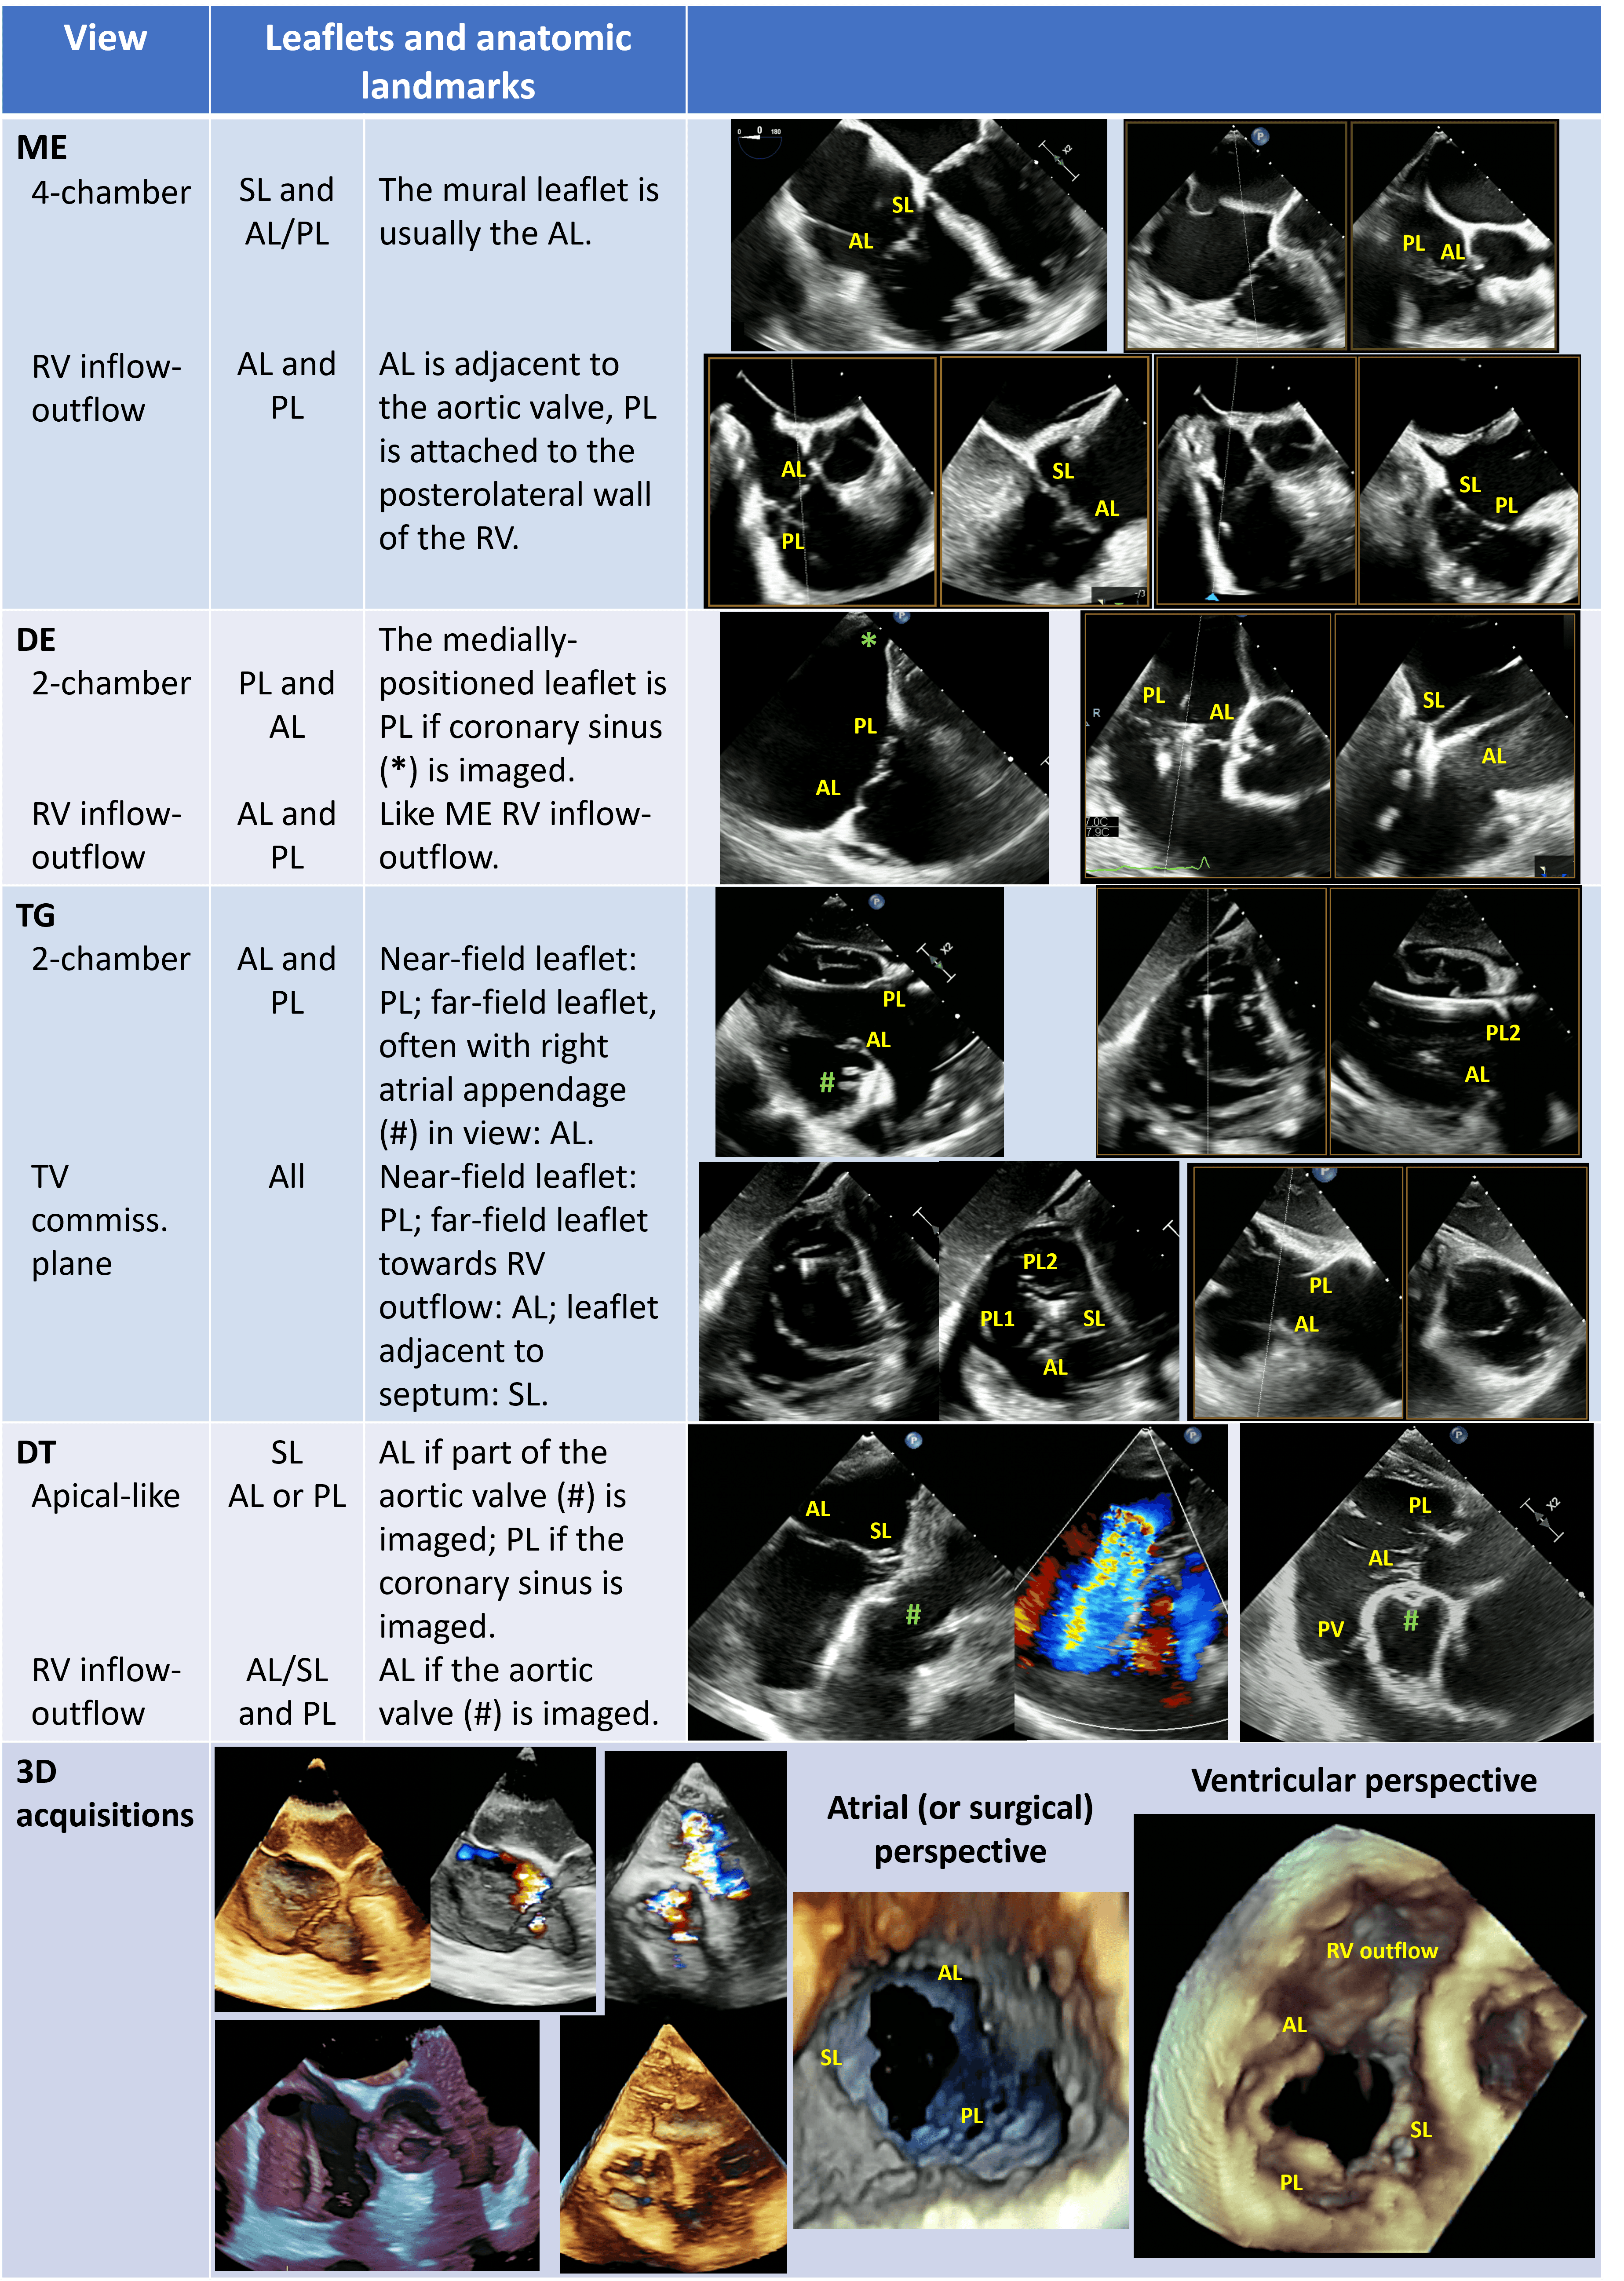

Here follow the procedural steps of TEER for TV, altogether with the main required TEE views (Fig. 8) [43, 59, 129].

Fig. 8.Steps of intraprocedural imaging. (A,B) Insertion of the steerable guide catheter into the right atrium. (C–E) Advancement of the clip delivery system through the steerable guide catheter into the right atrium and steering towards tricuspid valve plane. (F) Axial alignment of the clip delivery system. (G) Clip rotation and alignment to the coaptation line. (H,I) Leaflet grasping. (L–N) Check of adequate leaflet tissue grasping. (O,P) Assessment of residual TR. (Q) Clip deployment. (R) advancement of a second clip into the right atrium.

(1) Insertion of the steerable guide catheter into the RA (Fig. 8A,B): ME bicaval or modified bicaval (with TV in sight), TG LAX with entry point of IVC into RA in the view, 3D view of RA.

(2) Advancement of the clip delivery system through the steerable guide catheter into the RA and steering towards TV plane (Fig. 8C–E): same views of the first step plus the inflow-outflow view (or intercommissural view) with biplane (or cross-plane) mode for the steering manoeuvre towards the target lesion. The interaction of the clip delivery system and the clip itself with the interatrial septum have to be carefully followed to avoid a perforation of the interatrial septum. As the basic principle of TEER for TV is to approximate the mural leaflet to the septal one, which works as an anchor, the inflow-outflow view (ME or DE) is fundamental because, together with the biplane-derived 4 chamber views, it allows to entirely span the septal leaflet and to guide the clip in anterior-posterior and septal-lateral directions towards the target lesion.

(3) Axial alignment of the clip delivery system (Fig. 8F): ME or DE inflow-outflow views with biplane mode, TG views. The trajectory of the clip delivery system towards the target lesion should be properly adjusted so that the clip results perpendicular to the TV plane.

(4) Clip rotation and alignment to the coaptation line (Fig. 8G): TG with biplane mode (simultaneous assessment of SAX and LAX).

(5) Leaflet grasping (Fig. 8H,I): ME or DE inflow-outflow views with biplane mode with the primary plane positioned perpendicular to the clip arms showing the clip position along the coaptation line. As already mentioned, the inflow-outflow view is crucial for a successful tricuspid TEER procedure as it permits a quick and effective localization of the clip along the entire coaptation line with the septal leaflet.

(6) Check of adequate leaflet tissue grasping (Fig. 8L–N): TG with biplane mode (simultaneous assessment of SAX and LAX), ME or DE inflow-outflow views with biplane mode, ME 4-chamber and DE 2-chamber views, 3D imaging from any window and with additional use of real-time MPRs. The quality check of leaflet grasp is based on several factors: restriction of leaflet motion and clip stability on 2D imaging, adequate tissue bridge on 3D imaging, and TR reduction with colour-Doppler.

(7) Assessment of residual TR (Fig. 8O,P) and trans-valvular gradient (

(8) Clip deployment (Fig. 8Q): views of the previous step. After clip deployment a reassessment of clip stability and residual TR is necessary; the clip delivery system is then safely withdrawn under echocardiographic guidance unless another clip is needed (Fig. 8R).